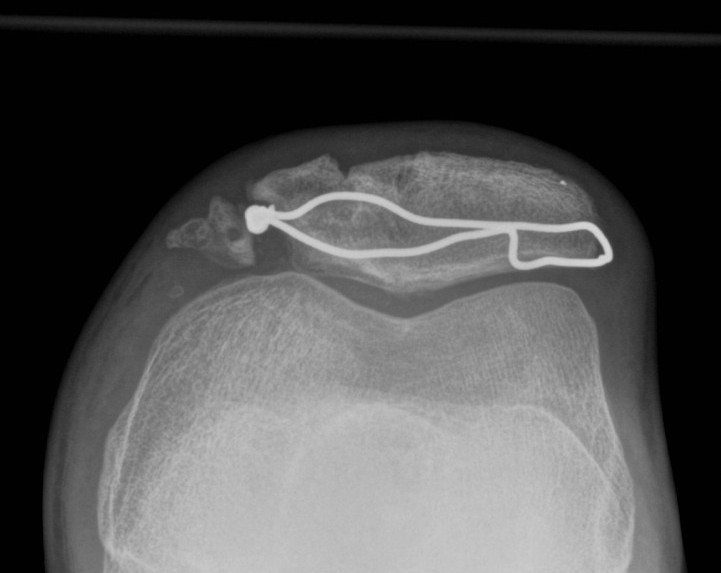

Lateral retinacular release

Indications

Lateral facet OA in setting of lateral tilt and tight lateral retinaculum

Technique

Vumedi arthroscopic lateral release technique